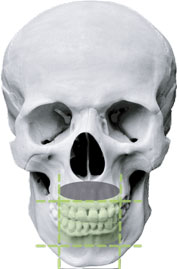

Green X предоставляет возможность выбора различных размеров поля обзора. Это позволяет пользователю настроить оптимальный режим сканирования и снизить облучение тех областей, которые не представляют интереса для диагностики. В зависимости от конкретных задач, можно выбрать размер поля обзора от 4х4 см до 18х15 см. Устройство подходит для диагностики зубных рядов, синусов, височно-нижнечелюстных суставов (ВНЧС) и большинства случаев челюстно-лицевой хирургии. Также имеется функция измерения объема дыхательных путей.